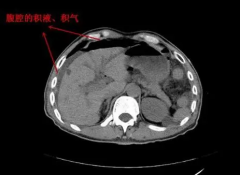

10. 引起腹腔积液的几种原因,积液24mm能做试管移植吗?

引起腹腔积液的几种原因,积液24mm能做试管移植吗?

腹腔积液是指在腹腔内积聚的液体。腹腔积液的大小可能会对移植产生影响,具体情况需要根据个体情况和医生的专业建议来确定。如果腹腔积液的大小超过了正常范围,可能会影响移植的进